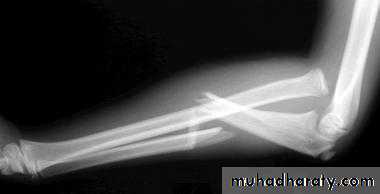

Upper limb

Fall on out stretched hand

xray